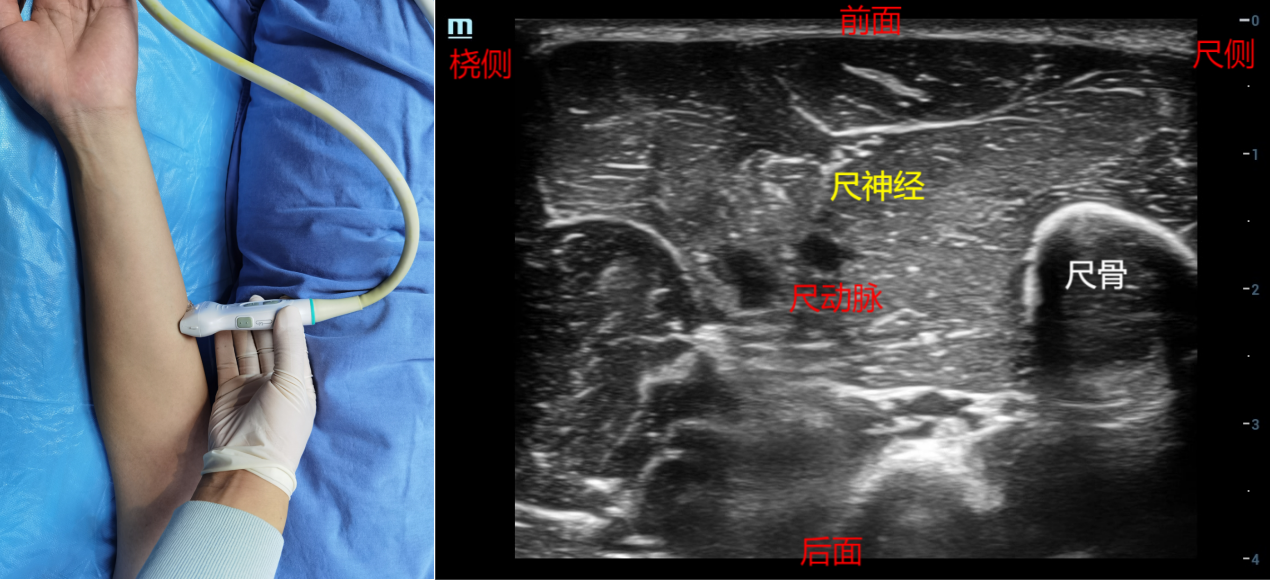

3、前臂入路:前臂入路的优点是能保留上肢的活动度。体位:肘关节伸直,前臂外旋,掌心向上。步骤:探头先在肘关节处找到尺神经,然后往远端平移探头追踪尺神经,在前臂中段处,在尺动脉附近,高回声梭形的声像为尺神经。由于在此处尺神经非常表浅,可以采用平面内法或者平面外法,从探头前端或方便进针一侧进针,药物注射在尺神经周围。药物用量:0.25%-0.5%罗哌卡因3-5ml。